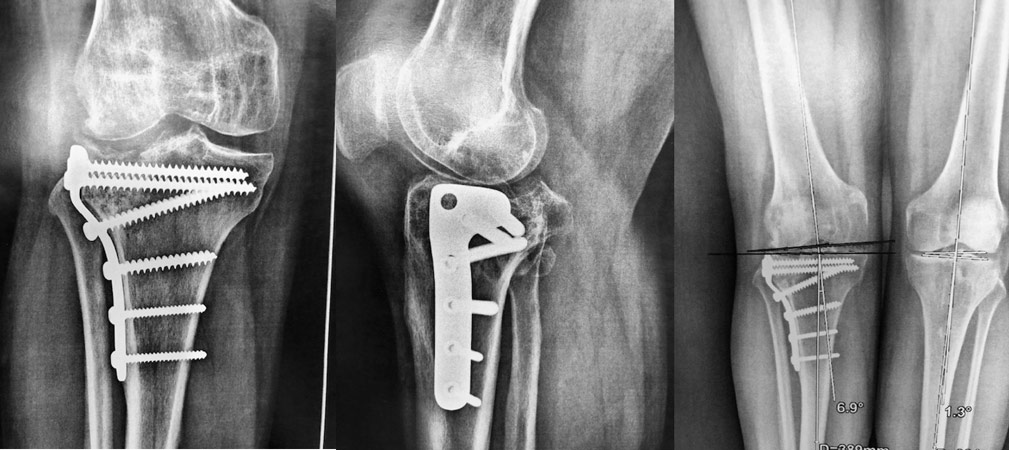

Indication d’ostéotomie pour ré-axer le genou.

On réalise une ostéotomie tibiale car la déformation est localisée sur le tibia, avec une plaque interne.

Arthrose externe, patiente jeune, genou en valgus (jambes en X), patiente jeune, on propose une ostéotomie pour ré-axer le genou.